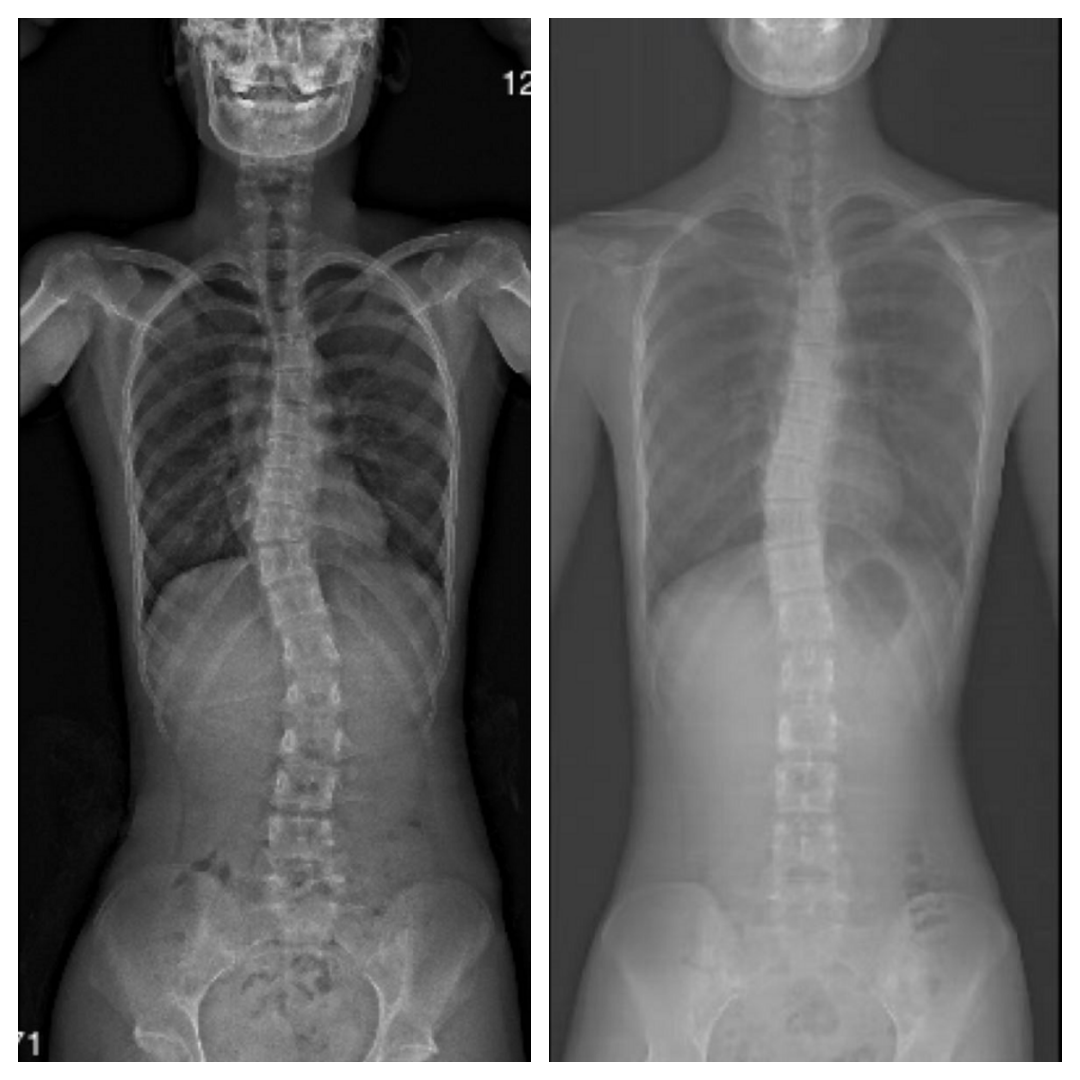

当玲第一次来到优复新天地国际医疗中心时,她和家人满怀焦虑与担忧。初次拍摄的X光片清晰揭示了她所面临的脊柱问题,为后续治疗提供了明确的方向。

初始X光片

这远不止是外观上的困扰。脊柱的异常弯曲可能带来慢性疼痛、限制肺部功能,并对长期健康与生活质量产生深远影响。我们的首要目标是为玲量身定制个性化的康复方案,遏制病情进展,同时最大程度地改善脊柱的力学排列。